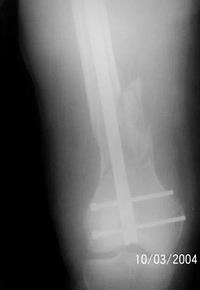

A 34 year old male was injured in a car accident.

The femur injury was treated by long retrograde interlocking nail.

I would expect healing though alignment could have been better if Poller screw or temporary wire was used.

It was used ORTHFIX Retrograde nailing System, diameter 11.